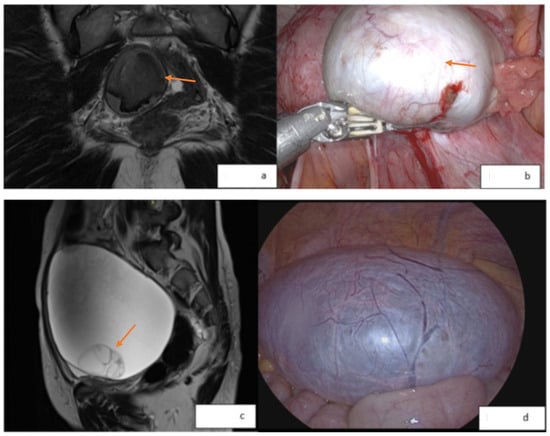

- Naem, A.; Shamandi, A.; Al-Shiekh, A.; Alsaid, B. Free large sized intra-abdominal endometrioma in a postmenopausal woman: A case report. BMC Women’s Health 2020, 20, 190. [Google Scholar] [CrossRef] [PubMed]

- Zografou, M.T.; Naem, A.; Laganà, A.S.; Krentel, H. A Large Ovarian Endometrioma Occupying the Abdominal Cavity in a Postmenopausal Patient: A Case Report. Medicina 2023, 59, 1398. [Google Scholar] [CrossRef] [PubMed]

| Naem [74] | 2020 | Benign abdominal endometrioma | A 67-year-old woman presented with bowel obstruction and right-sided hydronephrosis in the setting of a 17 × 26 cm abdominal mass. The patient underwent laparotomy with the en-bloc resection of the mass. |

| Zografou [76] | 2023 | Benign ovarian endometrioma | A 60-year-old previously healthy female presented with a 26 cm ovarian mass. Pre-operative Ca-125 was 512.9 U/mL, and all other labs were normal. The patient underwent laparotomy with BSO. |